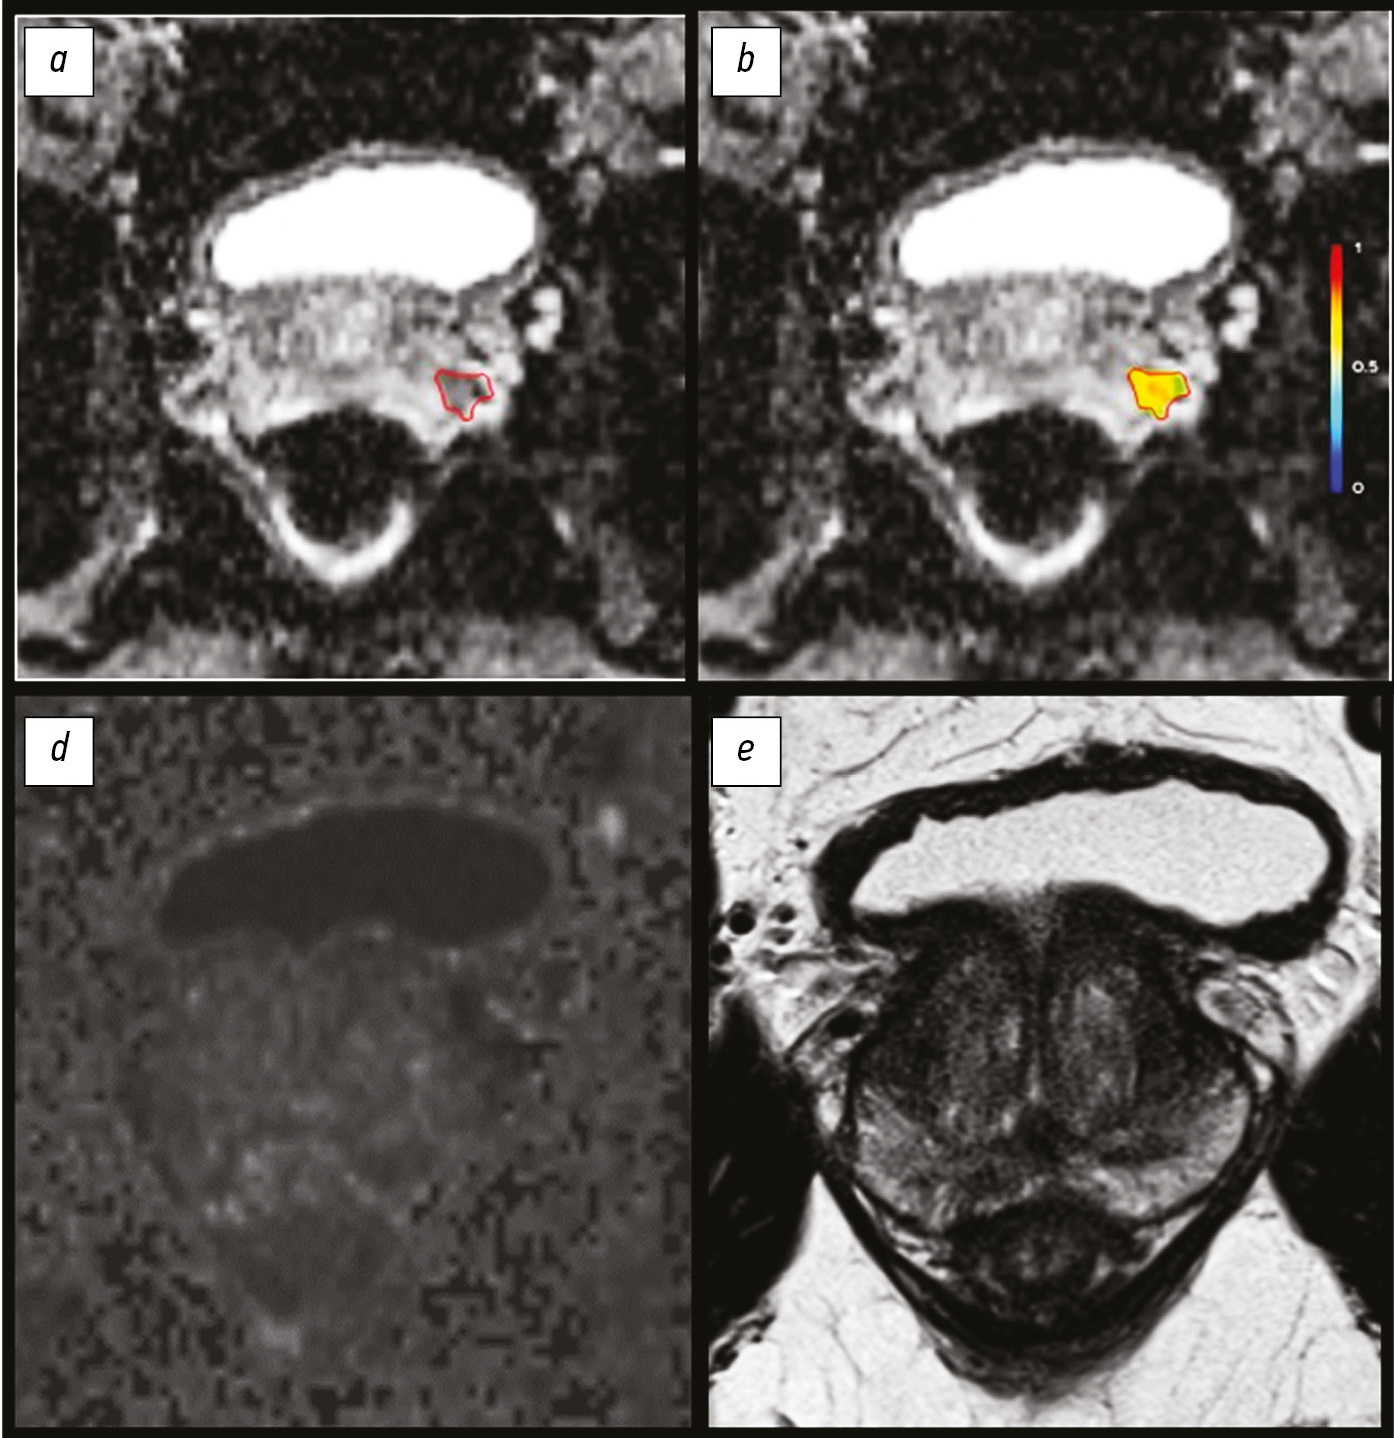

Радиомика магнитно-резонансной томографии при раке предстательной железы: что известно в настоящее время?

Подходы к диагностике и лечению рака предстательной железы опираются на комбинацию данных магнитно-резонансной томографии и гистологических данных.

Цель данного обзора ― введение читателя в основы современного диагностического подхода к раку предстательной железы при помощи магнитно-резонансной томографии с фокусом на текстурный анализ цифровых медицинских изображений.

Текстурный анализ позволяет оценить взаимосвязи между пикселями изображения с помощью математических методов, что даёт дополнительную информацию, в первую очередь о внутриопухолевой гетерогенности. Текстурный анализ признаков первого порядка может иметь бό́льшую клиническую воспроизводимость, чем текстурные характеристики более высокого порядка. Текстурные особенности, извлечённые из карт коэффициента диффузии, показали наибольшую клиническую значимость.

Будущие исследования должны быть направлены на интеграцию методов машинного обучения для облегчения использования текстурного анализа в клинической практике. Требуется развитие автоматизированных методов сегментации для уменьшения вероятности включения нормальных тканей в области интереса и ускорения получения результатов анализа. Для проверки диагностического потенциала текстурных признаков требуются крупные проспективные исследования.

Возрастающая роль функциональной визуализации для навигации радиотерапии и брахитерапии на примере рака предстательной железы

Аннотация

Брахитерапия успешно применяется в лечении злокачественных новообразований у мужчин и женщин, в редких случаях у детей, как самостоятельный метод (например, при локализованном раке предстательной железы) или адъювантный с дистанционной фокальной лучевой терапией (например, при раке шейки матки, анального канала, головы и шеи, молочной железы и пр.).

Расширение диагностических возможностей (появление компьютерной и магнитно-резонансной томографии) благодаря трёхмерной визуализации дало брахитерапии важное технологическое преимущество перед другими методами. Существует множество вариантов сочетания брахитерапии с дистанционной лучевой или системной противоопухолевой терапией в первой линии, а также в монорежиме при локализованном рецидиве опухоли в ранее облучённой зоне.

Введение интрастатов (полых трубок) для внутритканевой высокодозной брахитерапии осуществляется во время операции, а инкапсулированных (закрытых) радиоактивных микроисточников для низкодозовой брахитерапии ― напрямую (чрезкожно).

Отличительной спецификой брахитерапии является резкое падение дозы за пределами опухолевого очага, что минимизирует риск облучения окружающих органов и тканей.

Основным преимуществом брахитерапии в сравнении с дистанционной лучевой терапией является более высокий градиент дозы облучения на границе опухоли (со всех сторон). Более того, нет необходимости уточнения границ неопределённости при облучении мишени: когда опухоль изменяется в процессе лечения, то фиксированные в опухоли источники синхронно меняют своё положение.

Помимо преимуществ в эффективности и безопасности, совокупные финансовые затраты при брахитерапии существенно ниже других вариантов лучевой терапии.